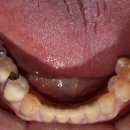

예약하고 방문했어요:-) 오랜만에 다른치과 방문에 신나더라구요ㅎㅎ 상태도 궁금해서 첫진료는 따라갔습니당😂 🔹부산 해운대구 좌동순환로 505 5층 덕바로치과의원 ☎️0507-1302-2806 🔹월~금 am9:00 - pm 6:00(목OFF) (점심시간 pm 12:30 - 2:00) 토 am9:00 - pm 2:30(점심시간x) 턱바로치과 : 네이버 블로그 구강...